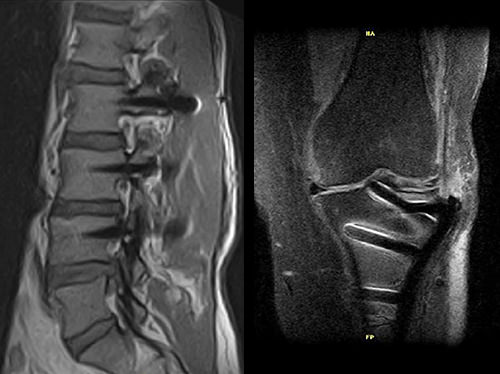

Pooperační zobrazování

Pacienti s kovovými implantáty tvoří stále větší část populace MRI. Magnifico MRI je optimální řešení, protože systém má přirozeně nízkou úroveň citlivosti na kovy ve srovnání s tradiční MRI.

Společně s vyhrazenými MAR sekvencemi nabízí Magnifico vysoce kvalitní diagnostiku také v přítomnosti většiny implantátů

Klinické snímky